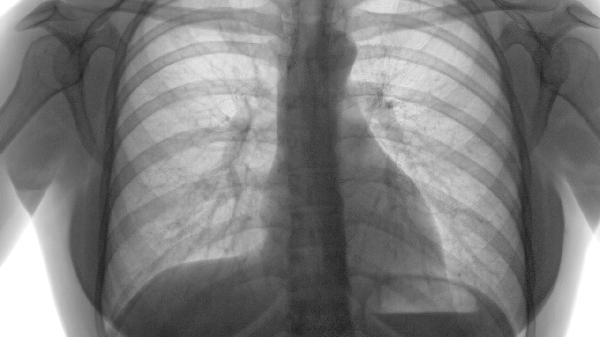

肺气肿本身是一种慢性肺部疾病,多数情况下由长期吸烟或空气污染等因素引起,主要表现为呼吸困难、咳嗽等症状。肺气肿可能由慢性支气管炎、长期吸烟、职业粉尘暴露、遗传因素、反复呼吸道感染等原因引起,通常表现为活动后气促、慢性咳嗽、咳痰等症状。

肺气肿症状主要表现为早期活动后气短、进展期持续性呼吸困难、终末期呼吸衰竭伴并发症。 1、早期表现: 轻度活动后气...

肺气肿常见症状包括气短、慢性咳嗽、胸闷、乏力等,病情发展可能出现桶状胸、体重下降等体征。 1、气短 早期表现为活...